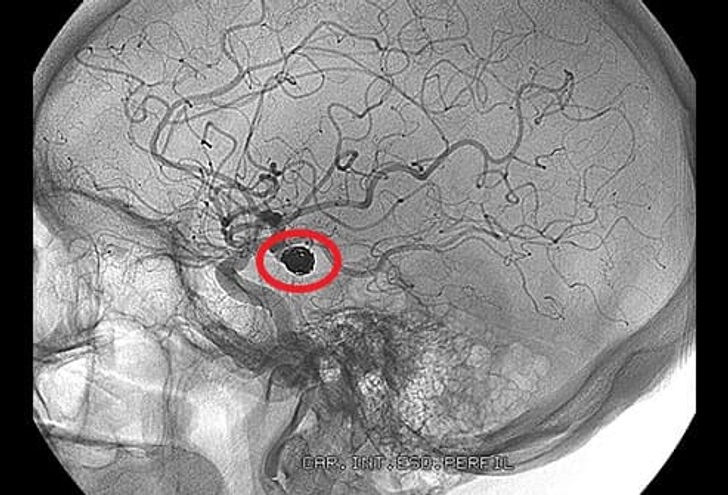

सीटी स्कैन और एमआरआईः थक्के की सही लोकेशन पता करने के लिए

एमआर एंजियोग्राफीः मस्तिष्क में ब्लॉकेज का पता लगाने के लिए